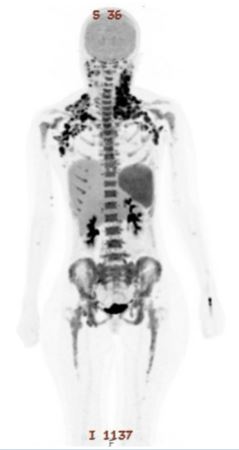

At day 28 evaluation, the bone marrow was hypocellular (10–20%) with 2% blasts. Minimal Residual Disease (MRD) analysis detected 0.7% residual myeloid population (CD117+, CD13+, CD33+, CD34^dim, HLA-DR+, CD15+, CD38+), while no T-lymphoblasts were identified. PET-CT demonstrated an excellent metabolic response with residual low-level uptake in bilateral cervical lymph nodes. Owing to persistent MRD and extramedullary activity, consolidation with Hyper-CVAD Part B ( High-dose Methotrexate and Cytarabine (Ara-C)) was administered in July 2025, together with continuation of venetoclax (Table 2). Repeat marrow examination demonstrated normocellularity (70–80%) with trilineage hematopoiesis and no morphologic or immunophenotypic evidence of disease; MRD was negative at the 0.01% threshold. Repeat PET scan showed complete metabolic resolution of prior (Figure 3).

Figure 3: PET-CT post HYPER-CVAD B + venetocloax demonstrated an excellent metabolic response with residual low-level uptake in bilateral cervical lymph nodes.

D+45 post-transplant assessment showed complete molecular remission on PET scan and Minimal Residual Disease (MRD) negativity by bone marrow biopsy (Figure 4).

Figure 4: PET CT post allogenic stem cell transplantation suggestive of a complete metabolic response.